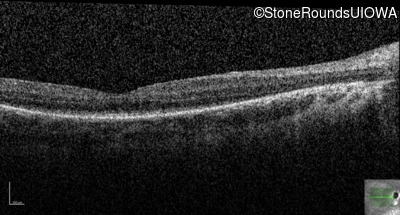

OD

OS

20/100 +1

OCT Stack

20/80 -2